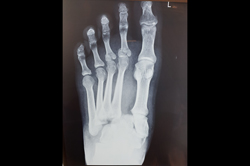

Metarsals with dislocations Lisfranc